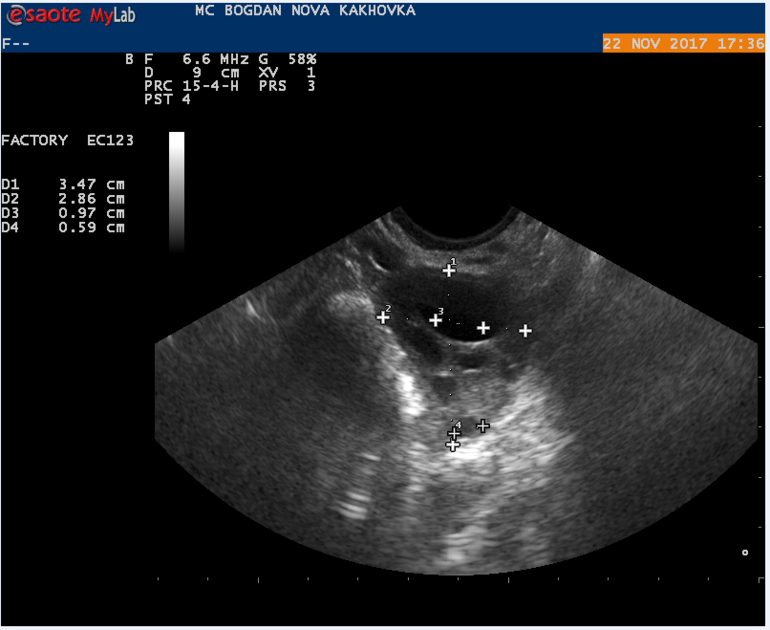

Мой результат УЗИ на 16 ДЦ Кто что может сказать? Тест на О положительный на 13 и 14 ДЦ.

в протоколе узи не слова о наличии доминантного фолликула, поэтому вряд ли была или будет овуляция в ближайшие дни

судя по узи овуляции не было,доминантного фолликула нет. хотя желтое тело может позже сформироваться